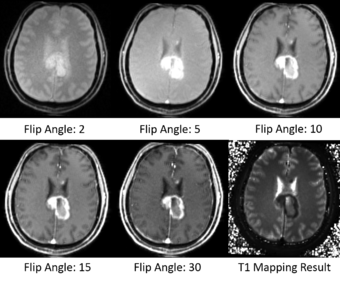

T1 mapping estimates effective tissue parameter maps (T1) from multi-spectral FLASH MRI scans with different flip angles. T1 mapping can be used to optimize parameters for a sequence, monitor diseased tissue, measure Ktrans in DCE-MRI and etc.

The method and equations for Variable Flip Angle T1 Mapping are available here: http://www.ncbi.nlm.nih.gov/pmc/articles/PMC3620726/pdf/nihms-423474.pdf

- Take multi-spectral FLASH images with an arbitrary number of flip angles as input, and estimate the T1 values of the data for each voxel.